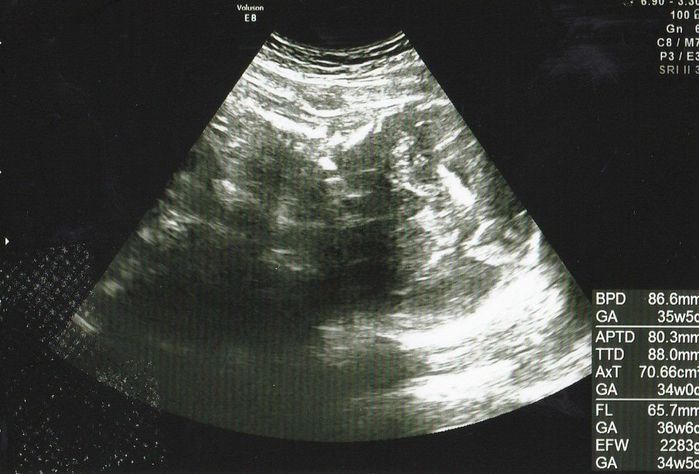

妊娠36週目エコー写真 「もう生まれても大丈夫」と、先生からお墨付き

推定体重=2878g

右側に頭、体は背中を向けて左側に、手を顔の前においているエコー画像です。赤ちゃんの体重はもうすぐ3kgというところ。先生から「(大きさとしては)もう生まれても大丈夫」と言われましたが、陣痛などの兆候は全くなく、出産がいつか、いつかとそわそわしていました。